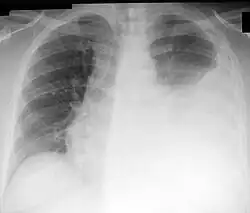

![]() Chest X-ray showing a left-sided pleural effusion (right side of image). This can be treated with thoracentesis. | |

Thoracentesis /ˌθɔːrəsɪnˈtiːsɪs/, also known as thoracocentesis (from Greek θώραξ (thōrax, GEN thōrakos) 'chest, thorax' and κέντησις (kentēsis) 'pricking, puncture'), pleural tap, needle thoracostomy, or needle decompression (often used term), is an invasive medical procedure to remove fluid or air from the pleural space for diagnostic or therapeutic purposes. A cannula, or hollow needle, is carefully introduced into the thorax, generally after administration of local anesthesia. The procedure was first performed by Morrill Wyman in 1850 and then described by Henry Ingersoll Bowditch in 1852.[1]

This procedure is indicated when unexplained fluid accumulates in the chest cavity outside the lung. In more than 90% of cases, analysis of pleural fluid yields clinically useful information. If a large amount of fluid is present, then this procedure can also be used therapeutically to remove that fluid and improve patient comfort and lung function.